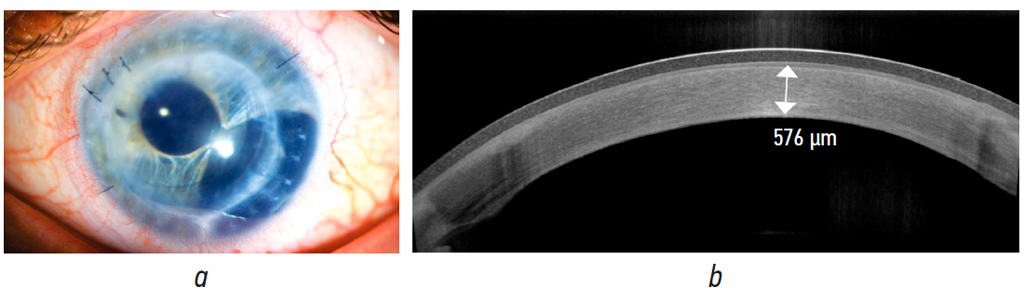

Case report No. 1

Penetrating graft edema completely resolved at postoperative month 3 (Fig. 5, a). BCVA was 0.1, IOP was 22 mmHg on hypotensive therapy (brinzolamide + timolol and brimonidine), central thickness of the penetrating graft based on OCT data was 576 μm (Fig. 5, b), and ECD was 1648 cells/mm2.

Fig. 5. Clinical case No. 1, 3 months after the modified transplantation of the endothelium on descemet membrane with a banded stromal flap: a, photo of the anterior segment of the eye, the corneal graft is transparent, the pupillary model of the hydrophilic IOL is transparent; b, OCT of the penetrating graft, central thickness of the penetrating graft is 576 µm

Рис. 5. Клинический случай № 1, через 3 мес. после модифицированной трансплантации эндотелия с десцеметовой мембраной с бандажным стромальным лоскутом: a — фото переднего отрезка глаза, сквозной трансплантат роговицы прозрачный, зрачковая модель гидрофильной интраокулярной линзы прозрачная; b — ОКТ сквозного трансплантата, центральная толщина сквозного трансплантата 576 мкм